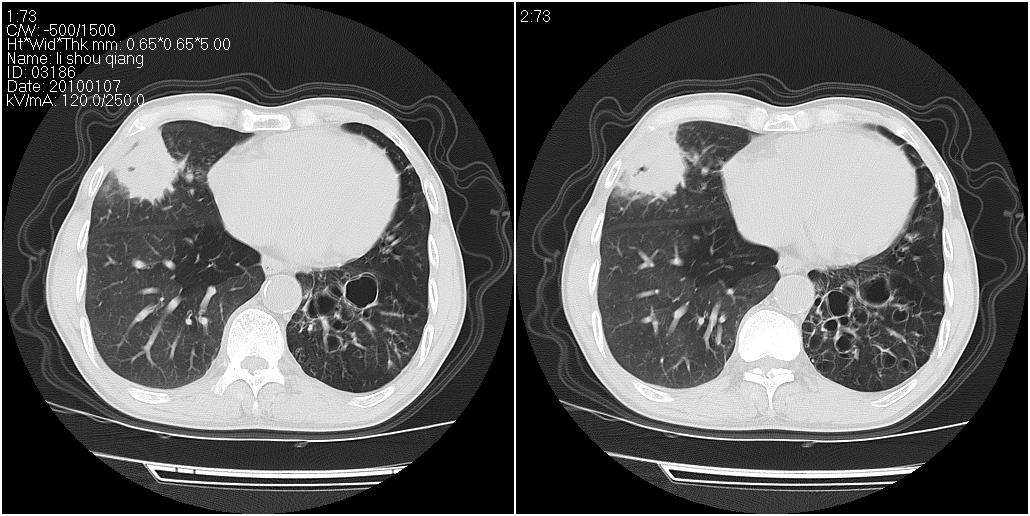

标题: CT24038:男性,58岁。主因咳嗽带血性CT检查。 [打印本页]

标题: CT24038:男性,58岁。主因咳嗽带血性CT检查。

右肺中叶外侧段见一不规则的软组织肿块,边缘可见毛刺,并见厚壁空洞,与胸膜分界欠清。另左下肺见多个小囊状扩张区

右肺中叶外侧段可见团块影,外形不规则,内见空泡征。左下肺见蜂窝状低密度透亮影,部分层面主动脉旁瘤样突出。考虑右肺中叶外围型肺癌可能性大,左下肺支气管扩张,主动脉弓瘤样突出。